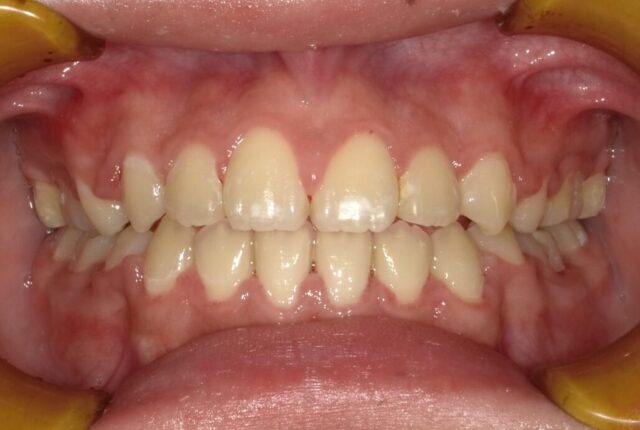

≪正面観≫

《動的治療期間1年8ヶ月》

before

after

| 診断名 | 上顎前歯部叢生を伴う下顎前突 開咬 |

| 初診時年齢・性別 | 10歳8ヶ月・女子 |

| 治療期間 | 1段階目:5カ月 経過観察:1年 2段階目:20ヶ月~ |

| 治療方法・治療内容 | 1段階目:フェイシャルマスク 2段階目:ストレートワイヤーテクニック |